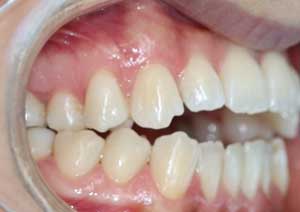

En orthodontie, une béance antérieure est une malocclusion caractérisée par l’absence de contact entre les incisives supérieures et inférieures lorsqu’on ferme les dents.

Traitement : Une ingression des molaires maxillaires avec une égression contrôlée du secteur antérieur a été réalisée à l’aide des arcs dits “Rocking Chair”, associés à des élastiques antérieurs portés de canine à canine, à droite et à gauche.

Cette mécanique permet de corriger la béance antérieure tout en conservant un contrôle précis de la position des dents antérieures et postérieures.

Avant